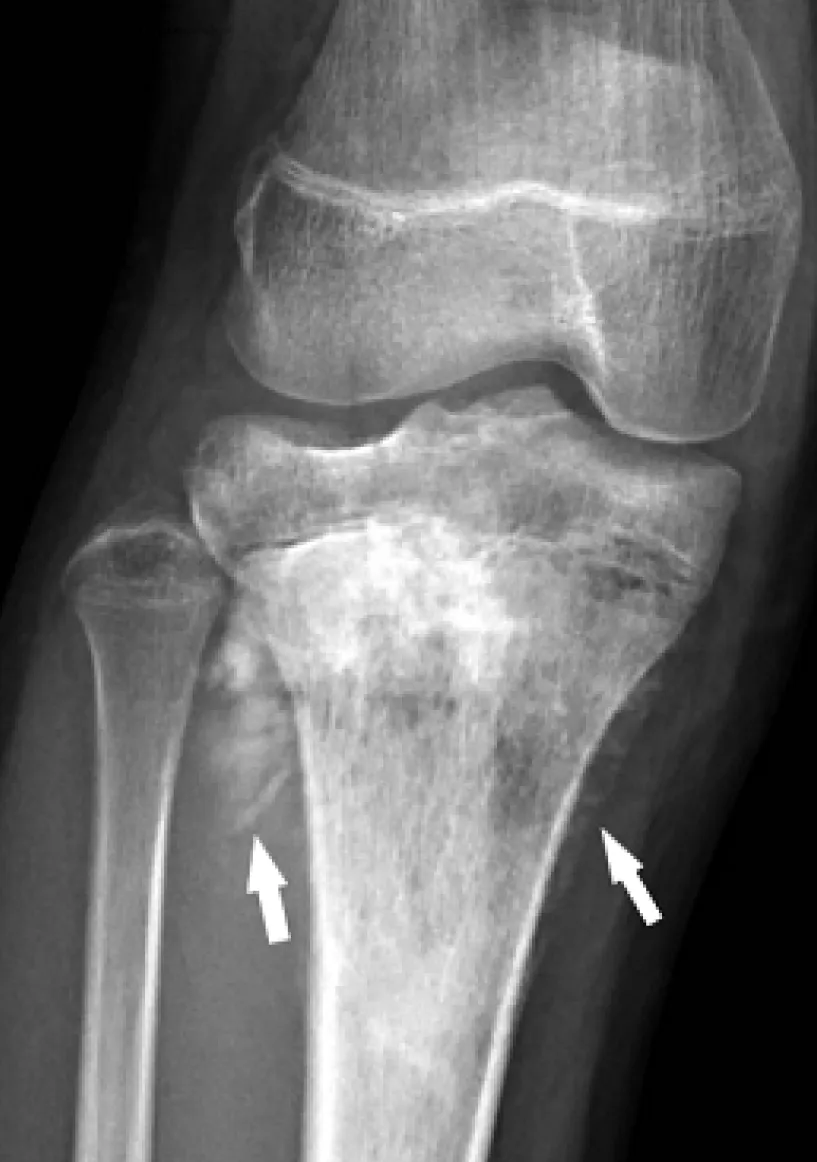

【114-1 醫學(五) 第73題】附圖是一位13歲女性脛骨骨肉瘤(osteosarcoma)的膝部X光影像,箭頭所指的影像表現是下列何者?